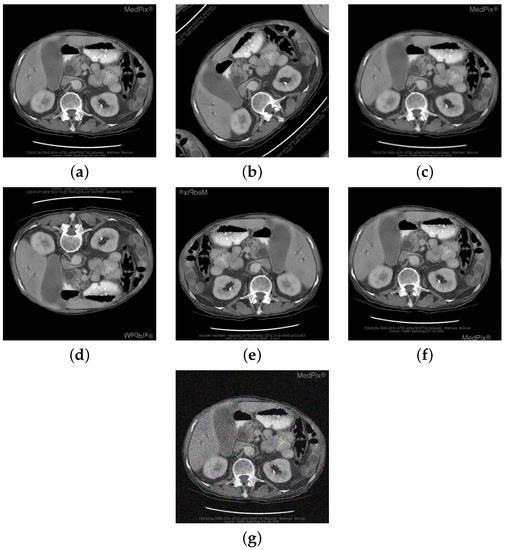

| Image | Category | Generated and Ground Truth Questions |

|---|---|---|

![]() | Abnormality | is a ring enhancing lesion present in the right lobe of the liver? is a ring enhancing lesion present in the right lobe of the liver? is the liver normal? |

![]() | Modality | was this mri taken with or without contrast? which ventricle is compressed by the t2-hyperintense? was this mri taken with or without contrast? |

![]() | Organ | is this a typical liver? are these normal laughed kidneys? Is this a study of the brain? |

![]() | Plane | what plane is this image obtained? what plane is this image blood-samples? Is this image of a saggital plane? |